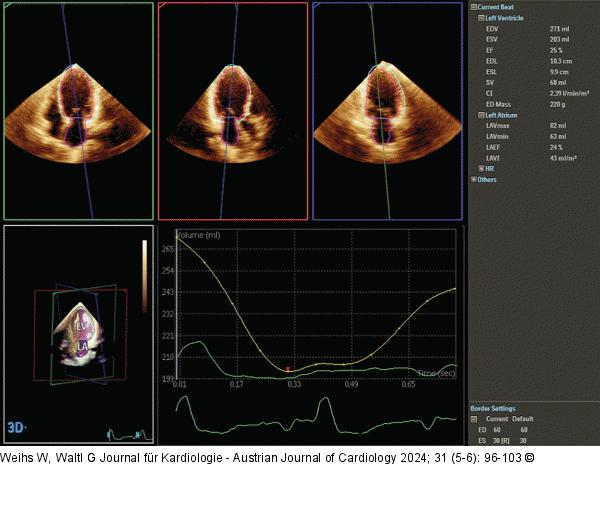

Abbildung 6: Echo Semiautomatische Quantifizierung der LV-Volumina und -EF im 3DE. |

Semiautomatische Quantifizierung der LV-Volumina und -EF im 3DE. |